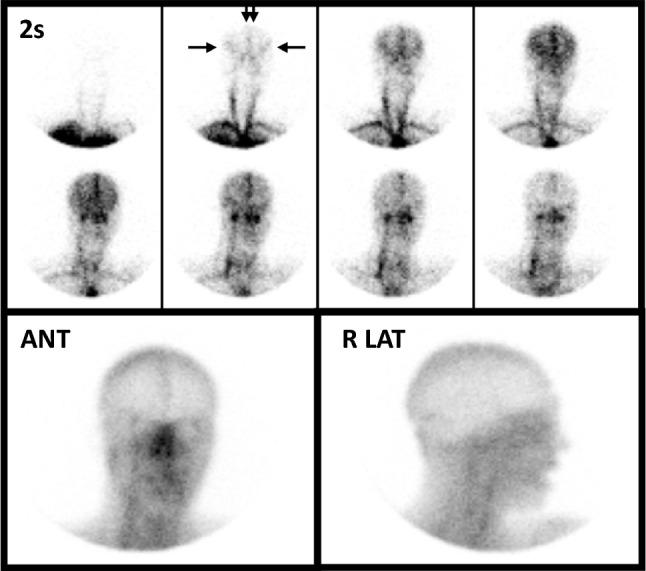

Radionuclide perfusion studies have an established ancillary role in determination of death by neurologic criteria (DNC). While critically important, these examinations are not well understood by individuals outside of the imaging specialties. The purpose of this review is to clarify relevant concepts and nomenclature and provide a lexicon of relevant terminology of value to non-nuclear medicine practitioners who wish to better understand these examinations. Radionuclides were first employed to evaluate cerebral blood flow in 1969. Radionuclide DNC examinations that use lipophobic radiopharmaceuticals (RPs) entail a flow phase followed immediately by blood pool images. On flow imaging, presence of intracranial activity within the arterial vasculature is scrutinized following arrival of the RP bolus into the neck. Lipophilic RPs designed for functional brain imaging were introduced to nuclear medicine in the 1980s and were engineered to cross the blood-brain-barrier and be retained in the parenchyma. The lipophilic RP Tc-hexamethylpropyleneamine oxime (Tc-HMPAO) was first used as an ancillary investigation in DNC in 1986. Examinations using lipophilic RPs entail both flow and parenchymal phase images. According to some guidelines, parenchymal phase uptake should be assessed by tomographic imaging, while other investigators consider simple planar imaging sufficient. Findings of perfusion on either the flow or parenchymal phase of the examination effectively precludes DNC. If the flow phase is omitted or somehow compromised, the parenchymal phase remains sufficient for DNC. A priori, parenchymal phase imaging is superior to flow phase imaging for several reasons and lipophilic RPs are favoured over lipophobic RPs in that both flow and parenchymal phase imaging are performed. Disadvantages of lipophilic RPs are increased cost and the need to procure them from a central laboratory, which can prove difficult, especially outside usual working hours. According to most current guidelines, both lipophilic and lipophobic RP categories are acceptable for use in ancillary investigations in DNC, with a growing overt preference for studies using the lipophilic RPs based on their ability to capture the parenchymal phase. The new adult and pediatric Canadian recommendations favour use of lipophilic RPs to variable degrees, specifically Tc-HMPAO, the lipophilic moiety which has undergone the greatest validation. Although ancillary use of radiopharmaceuticals is quite settled in multiple DNC guidelines and best practices, several areas of further research remain open to investigation. Examens auxiliaires de perfusion nucléaire pour la détermination du décès selon des critères neurologiques : méthodes, interprétation et lexique-un guide de l'utilisateur à l'intention du clinicien.